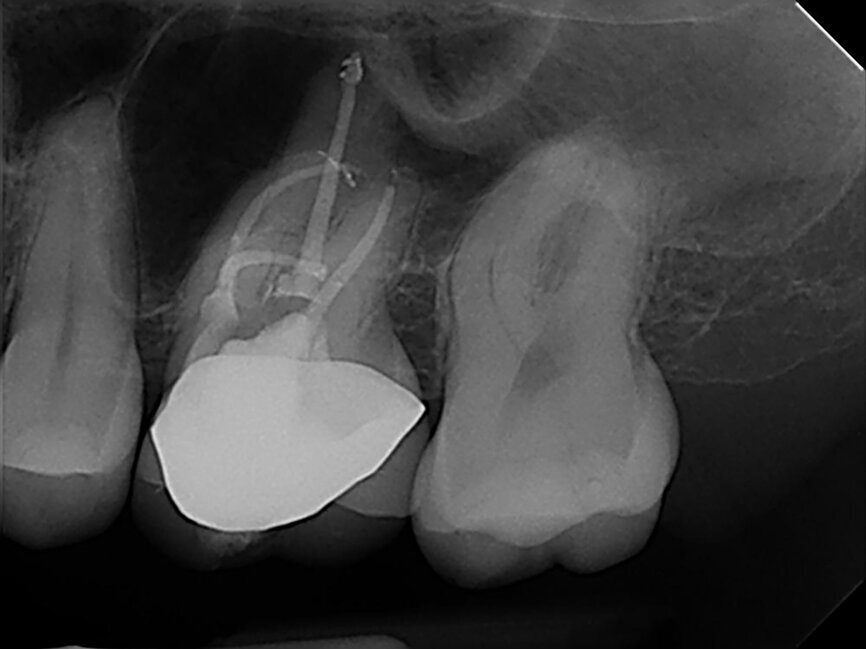

I instrumented the second mesiobuccal canal up to a 35 file following the same sequence, using sodium hypochlorite, first going up to a 15 file and employing the crown-down technique to a 35 file. After that, I irrigated with sodium hypochlorite, EDTA and chlorhexidine, dried the canal with sterile paper points, and took a radiograph to check the cone fit, again employing Gutta Percha Points and AH Plus (Fig. 3).

After confirming my satisfaction on the diagnostic intermediate radiograph, I used vertical condensation, leaving 4 mm of the apical portion of the cone and then backfilling with Gutta Percha Points. After that, as always, I placed an orifice barrier (PermaFlo Purple, Ultradent Products), followed by a cotton pellet.